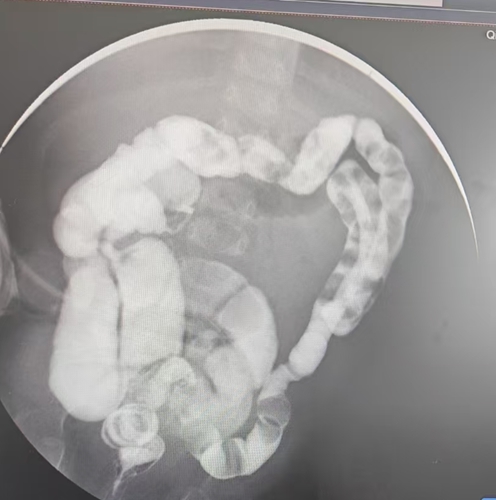

顏顏的人生從一開始就布滿荊棘。出生后,她因無法排出胎便,伴隨腹脹、嘔吐等癥狀,在當(dāng)?shù)蒯t(yī)院被確診為先天性巨結(jié)腸 —— 且是該病癥中最罕見也最嚴(yán)重的類型:全腸型先天性巨結(jié)腸,其發(fā)病率僅占所有先天性巨結(jié)腸病例的 1%-2%。

檢查結(jié)果不盡人意 —— 近3米長的腸道中,健康部分僅有15 公分!這意味著顏顏成了“短腸寶寶”,且病情尤其復(fù)雜嚴(yán)重,治療起來極為棘手。

針對(duì)顏顏的病情,新生兒外科宋華主任團(tuán)隊(duì)迅速制定了分階段治療方案。在保守治療滿一個(gè)月后,團(tuán)隊(duì)為她實(shí)施了第一次手術(shù)。術(shù)中不僅完成了回腸雙腔造瘺,還進(jìn)行了腸切除與腸吻合操作;術(shù)后腸活檢結(jié)果顯示,顏顏全腸神經(jīng)節(jié)細(xì)胞稀少 —— 這正是導(dǎo)致她腸道無法正常蠕動(dòng)的核心原因。

前不久,顏顏再次入院接受治療。新生兒外科宋華主任團(tuán)隊(duì)又為她實(shí)施了腹腔鏡下先天性巨結(jié)腸根治術(shù),不僅關(guān)閉了剩余的造瘺口,還精準(zhǔn)切除了一米多的病變腸段。